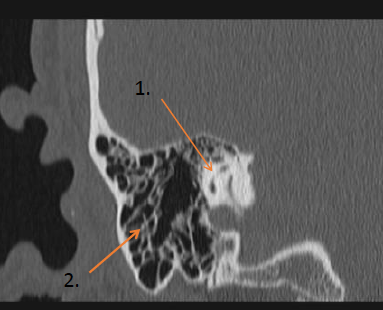

Identify the labeled structures: